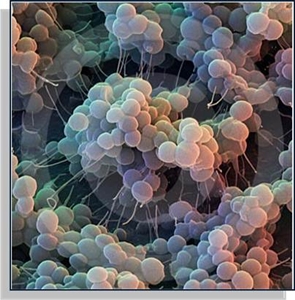

Agentes patogénicos

Os agentes patogénicos são microrganismos como bactérias, vírus, fungos, protozoários, vermes intestinais e outros tipos de vermes. Os agentes patogénicos são capazes de produzir doenças infecciosas aos seus hospedeiros, sempre que estejam em circunstâncias favoráveis, inclusive do meio ambiente. Um agente patogénico pode-se multiplicar no organismo do seu hospedeiro podendo causar infecção e outras complicações, pode ser chamado de agente infeccioso. A bromatologia forense identifica esses agentes, como por exemplo, em líquidos ou em algum alimento que possa ter sido ingerido. Na natureza, os agentes patogénicos convivem com as plantas desde o início da vida e têm a função ecológica de eliminar os indivíduos menos adaptados. Eles multiplicam-se anormalmente em situações de desequilíbrio e contribuem para o evoluir de uma situação instável. Os ecossistemas humanizados não são ecossistemas em equilíbrio, daí que a sua presença seja muitas vezes indesejada por colocar em risco os indivíduos que desejamos cultivar – as nossas plantas agrícolas ou ornamentais. Mesmo assim há inúmeras formas de tentar utilizar os processos naturais de controlo para que a sua multiplicação não se torne problemática.

Figura 1 – Agente patogénico.